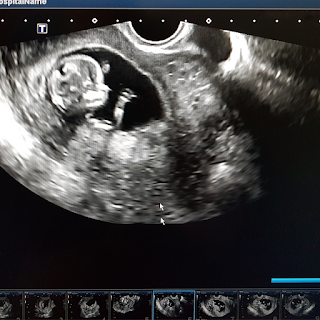

During the first trimester, a fertilized egg undergoes rapid cell division and implants itself into the uterine wall. This miraculous process gives rise to layers of cells that eventually form the embryo. By the sixth week, a tiny heartbeat can be detected, marking a significant milestone. As you approach the end of the first trimester (around week 12), your baby's bones, muscles, and organs take shape, transitioning from an embryo to a fetus.

Your baby experiences the most rapid growth during the first trimester. By the end of this phase, the fetus can weigh approximately 0.5 to 1 ounce and measure an average length of 3 to 4 inches. It's truly remarkable how quickly they develop!